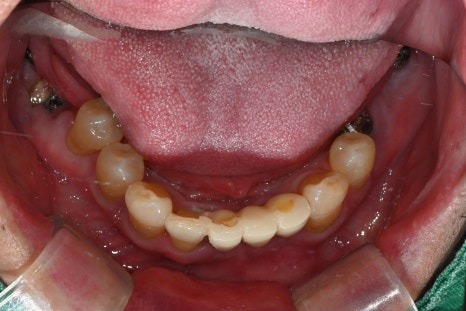

임시치아부터 최종 보철까지의 과정

수술 직후에는

임시틀니 대신 고정형 임시치아를 적용하여

일상생활과 식사 불편을 최대한 줄였습니다.

· 수술 다음 날 임시치아 장착

· 하악 일부는 2개월 내 조기 보철 완성

· 상악은 뼈이식 안정화를 충분히 거쳐 진행

전신질환이 있어

치료 기간이 길어질 가능성도 고려했으나,

6개월 내 안정적으로

보철을 마무리할 수 있었습니다.

수술 후 4개월